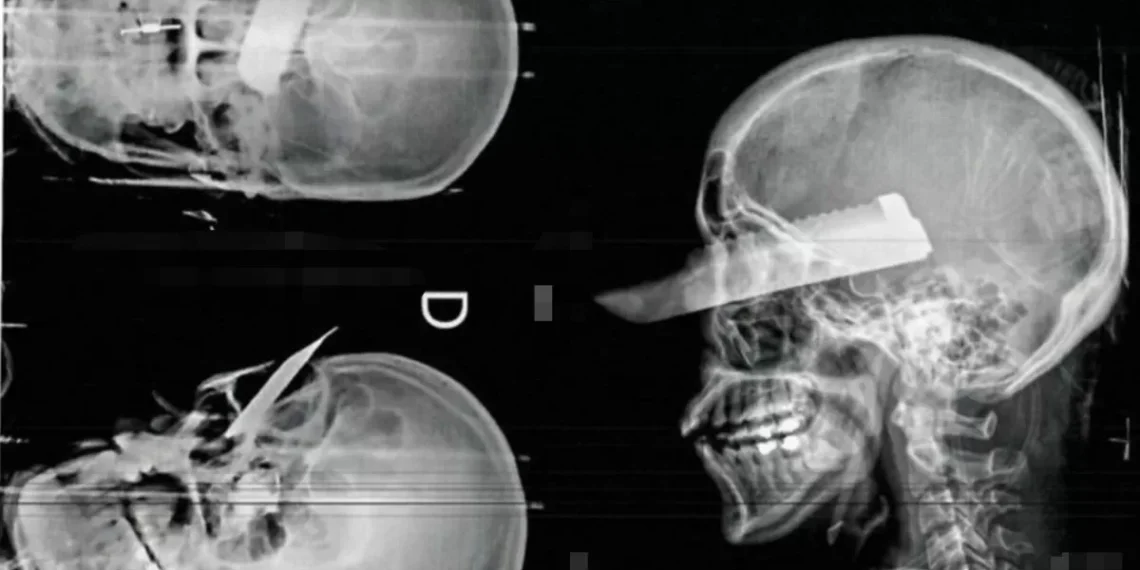

Durante a manhã, a violência atingiu um nível ainda mais assustador. O homem, visivelmente alterado, desferiu golpes com uma faca na direção da mulher. De acordo com a vítima, ele tentou acertar seu coração e sua garganta, mas ela conseguiu se defender e sofreu ferimentos nas mãos, braços e pescoço.

A mulher foi encaminhada para o hospital e passou por cirurgia para reparar os ferimentos causados pelo ataque. Segundo informações dos médicos, ela passa bem e não corre risco de vida.